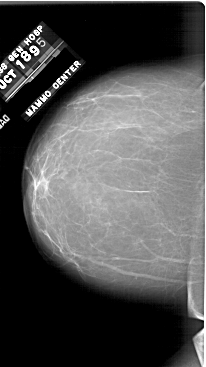

A_1748_1.RIGHT_MLO

RIGHT_MLO LINES 6616 PIXELS_PER_LINE 3721 BITS_PER_PIXEL 12 RESOLUTION 43.5 OVERLAY